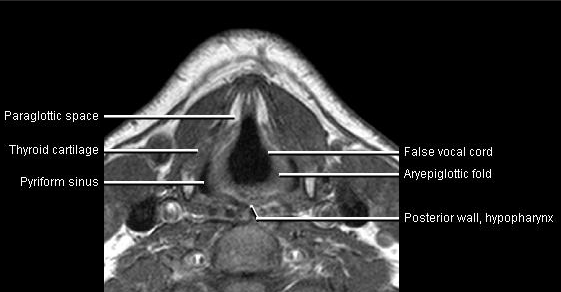

Phonation and dysphagia involve multiple coordinated structures in the larynx and pharynx. Radiation induced dysphagis appears to be related to dose to the phyaryngeal constrictor muscles and specific regions of the supraglottic and glottin larynyx.

Speech is impacted by doses to the epiglottis, base of tongue, aryepiglottic folds, false vocal cords upper esophageal sphincter and cricoid cartilage.

AnatomyCTMR